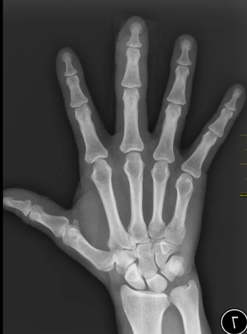

Cough, fever, cold, and body pain since yesterday

Diagnosis: Pneumonia

Certainty: Almost Certain

Author: Sadia Noreen

Date Published: Jan 23, 2025

Disease Specialty: Pulmonology

Image Type:

X Ray